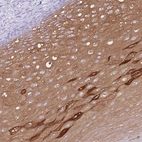

Immunohistochemical staining of human oral mucosa shows moderate cytoplasmic positivity in squamous epithelial cells.